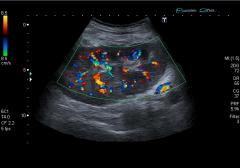

Paciente de sexo femenino de 23 años de edad, con ingesta de anticonceptivos orales, sin antecedentes clínicos ni quirúrgicos de importancia.

Consulta por dolor , aumento del perímetro abdominal y constipación de 3 meses de evolución. En el laboratorio presenta leucocitosis como único dato positivo.

Se le solicita una ecografía abdominal y Doppler hepático.

A) ¿Cuál es su diagnóstico? ¿A que corresponden las imágenes descriptas en la figura 1 y 2?

B) ¿Es posible inferir el tiempo de evolución de este proceso de acuerdo a los videos presentados?